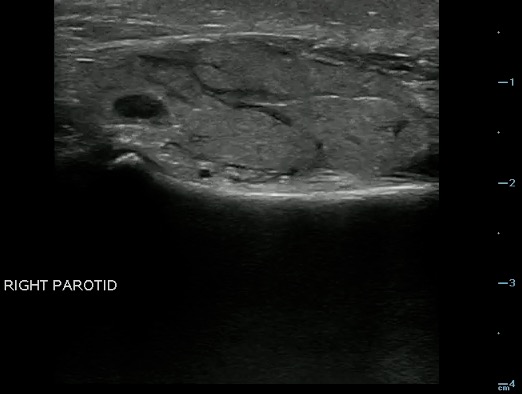

- Figure 18. Normal parotid gland (marked with arrow)

Video 12. Normal parotid gland

- Sonographically, the normal parotid and submandibular glands appear homogeneous; the fatty glandular tissue composition causes an increased echogenicity relative to adjacent muscle.

- Parotid Gland:

- The homogeneity and echogenicity of the parotid gland is comparable to that of the thyroid gland.

- Normal intraglandular salivary ducts and the Stensen’s duct are generally not visualized with ultrasound.

- Parotid short axis should be less than 5– 6 mm normally.13

- Figure 19 and 20. Parotid gland lymph nodes

Video 14. Parotid gland lymph nodes